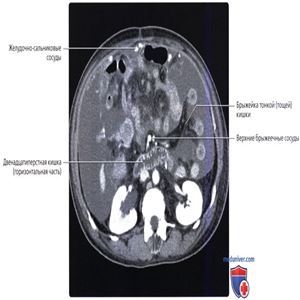

Обратите внимание на забрюшинное положение двенадцатиперстной кишки. Горизонтальная часть двенадцатиперстной кишки проходит позади верхних брыжеечных сосудов, кровоснабжающих тонкую кишку. Ветви брыжеечных сосудов лежат между листкам брыжейки и окружены жировой тканью.